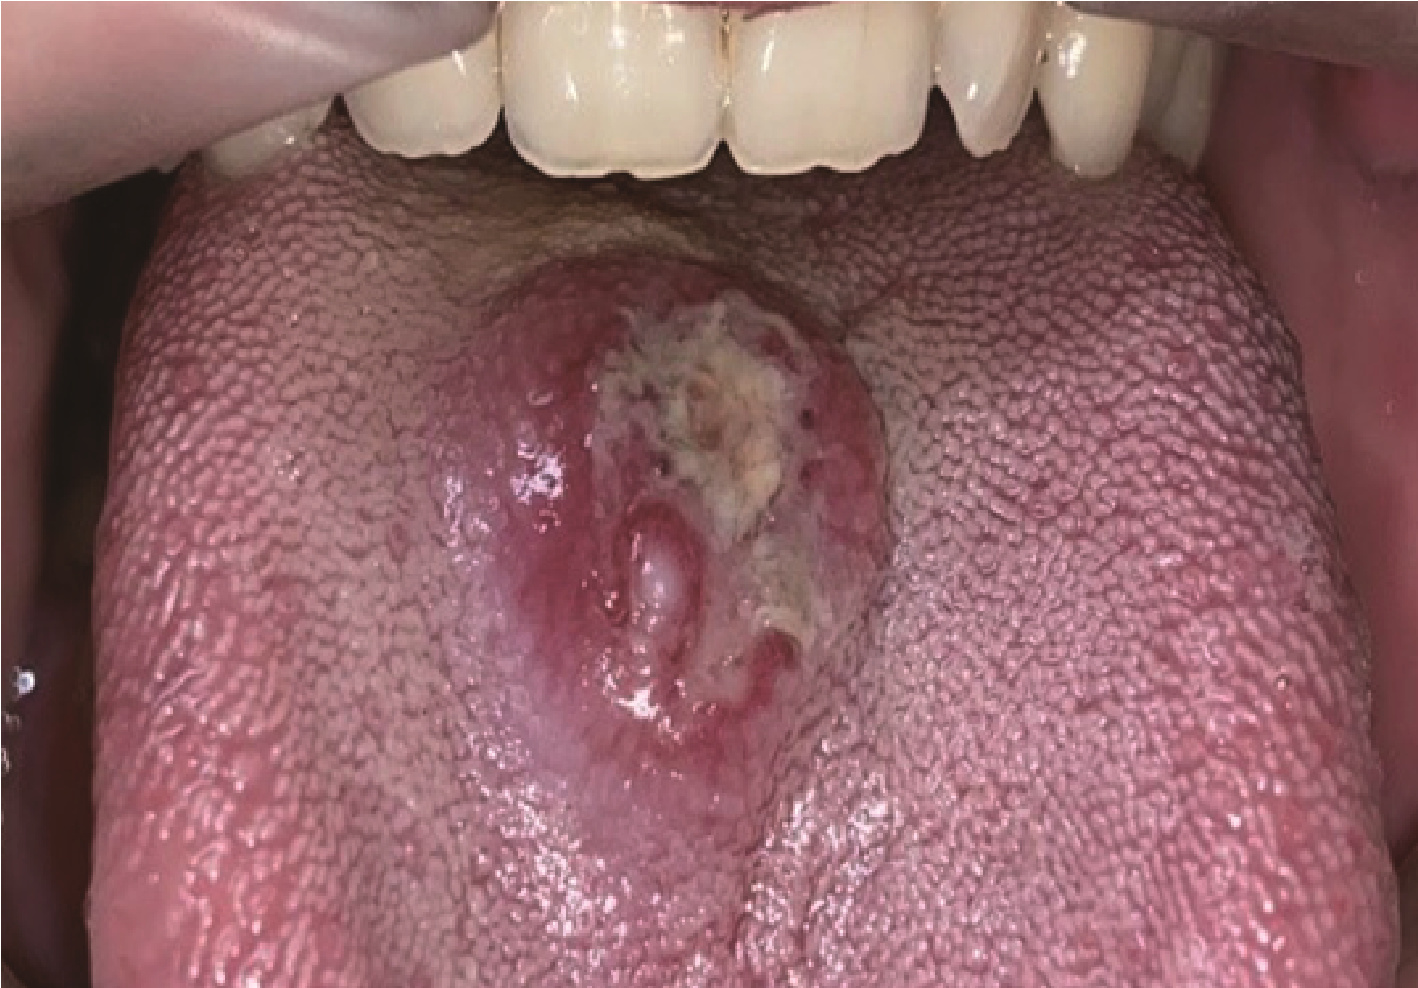

Figure 1

Case 1, an ulcer on the dorsum of the tongue, which is covered with pseudomembrane and surrounded by elevated lesion"